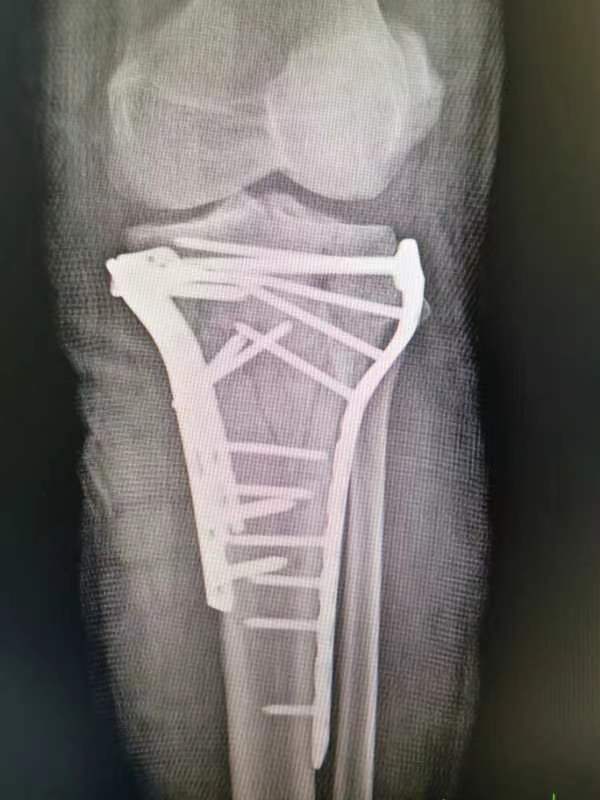

胫骨平台粉碎性骨折术前术后